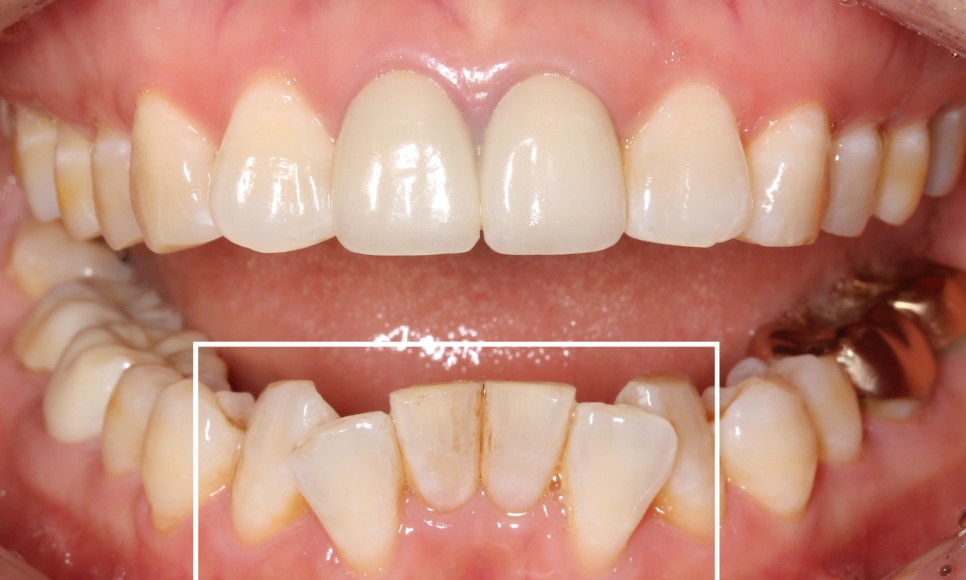

반면, 윗니는 아랫니에 비해

비교적 가지런한 상태였는데요.

이렇게 윗니는 고른 편인데

아랫니만 삐뚤어짐이 심한 상태일 땐

교정 정밀진단을 통해

아랫니만 2D교정 (설측 부분교정)으로

개선이 가능합니다.

아랫니 부분교정 치료 후

2D치과 2D교정 전후사진

짜잔~!

아랫니 부분교정이 끝난 뒤의

치아 모습입니다.

약 9개월 정도 소요되었는데요^^

삐뚤거리던 아랫니가

정말 많이 정리된 모습이죠?

들쭉날쭉하던 아랫니의 전치부도

아랫니 2D교정으로

고르게 펼쳐진 모습입니다.

윗니에 가려져서

거의 보이지 않았던 아랫니도

2D부분교정을 통해

정상적인 교합상태로 바뀌었습니다.

과하게 물리는 모습이

많이 개선되었죠?